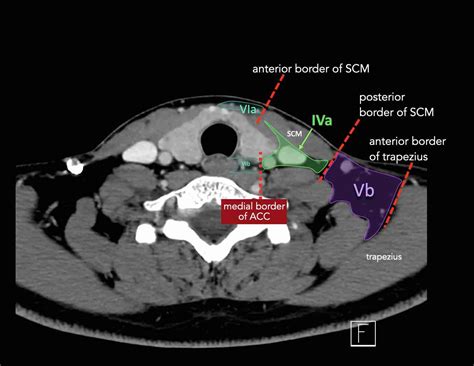

A CT of thorax, or computed tomography scan of the chest, uses X-rays and computer technology to create cross-sectional images of the thoracic cavity. These images provide a detailed view of the lungs, heart, blood vessels, and other structures within the chest. The procedure is particularly useful for diagnosing conditions such as lung cancer, pneumonia, and heart disease.

Interpreting the results of a CT of thorax involves a radiologist reviewing the images to identify any abnormalities. The findings are then communicated to the referring physician, who will discuss them with the patient. Common conditions that can be detected include:

Radiologists use advanced software to analyze the images, providing detailed reports that guide further treatment and management.

• ct of thorax anatomy